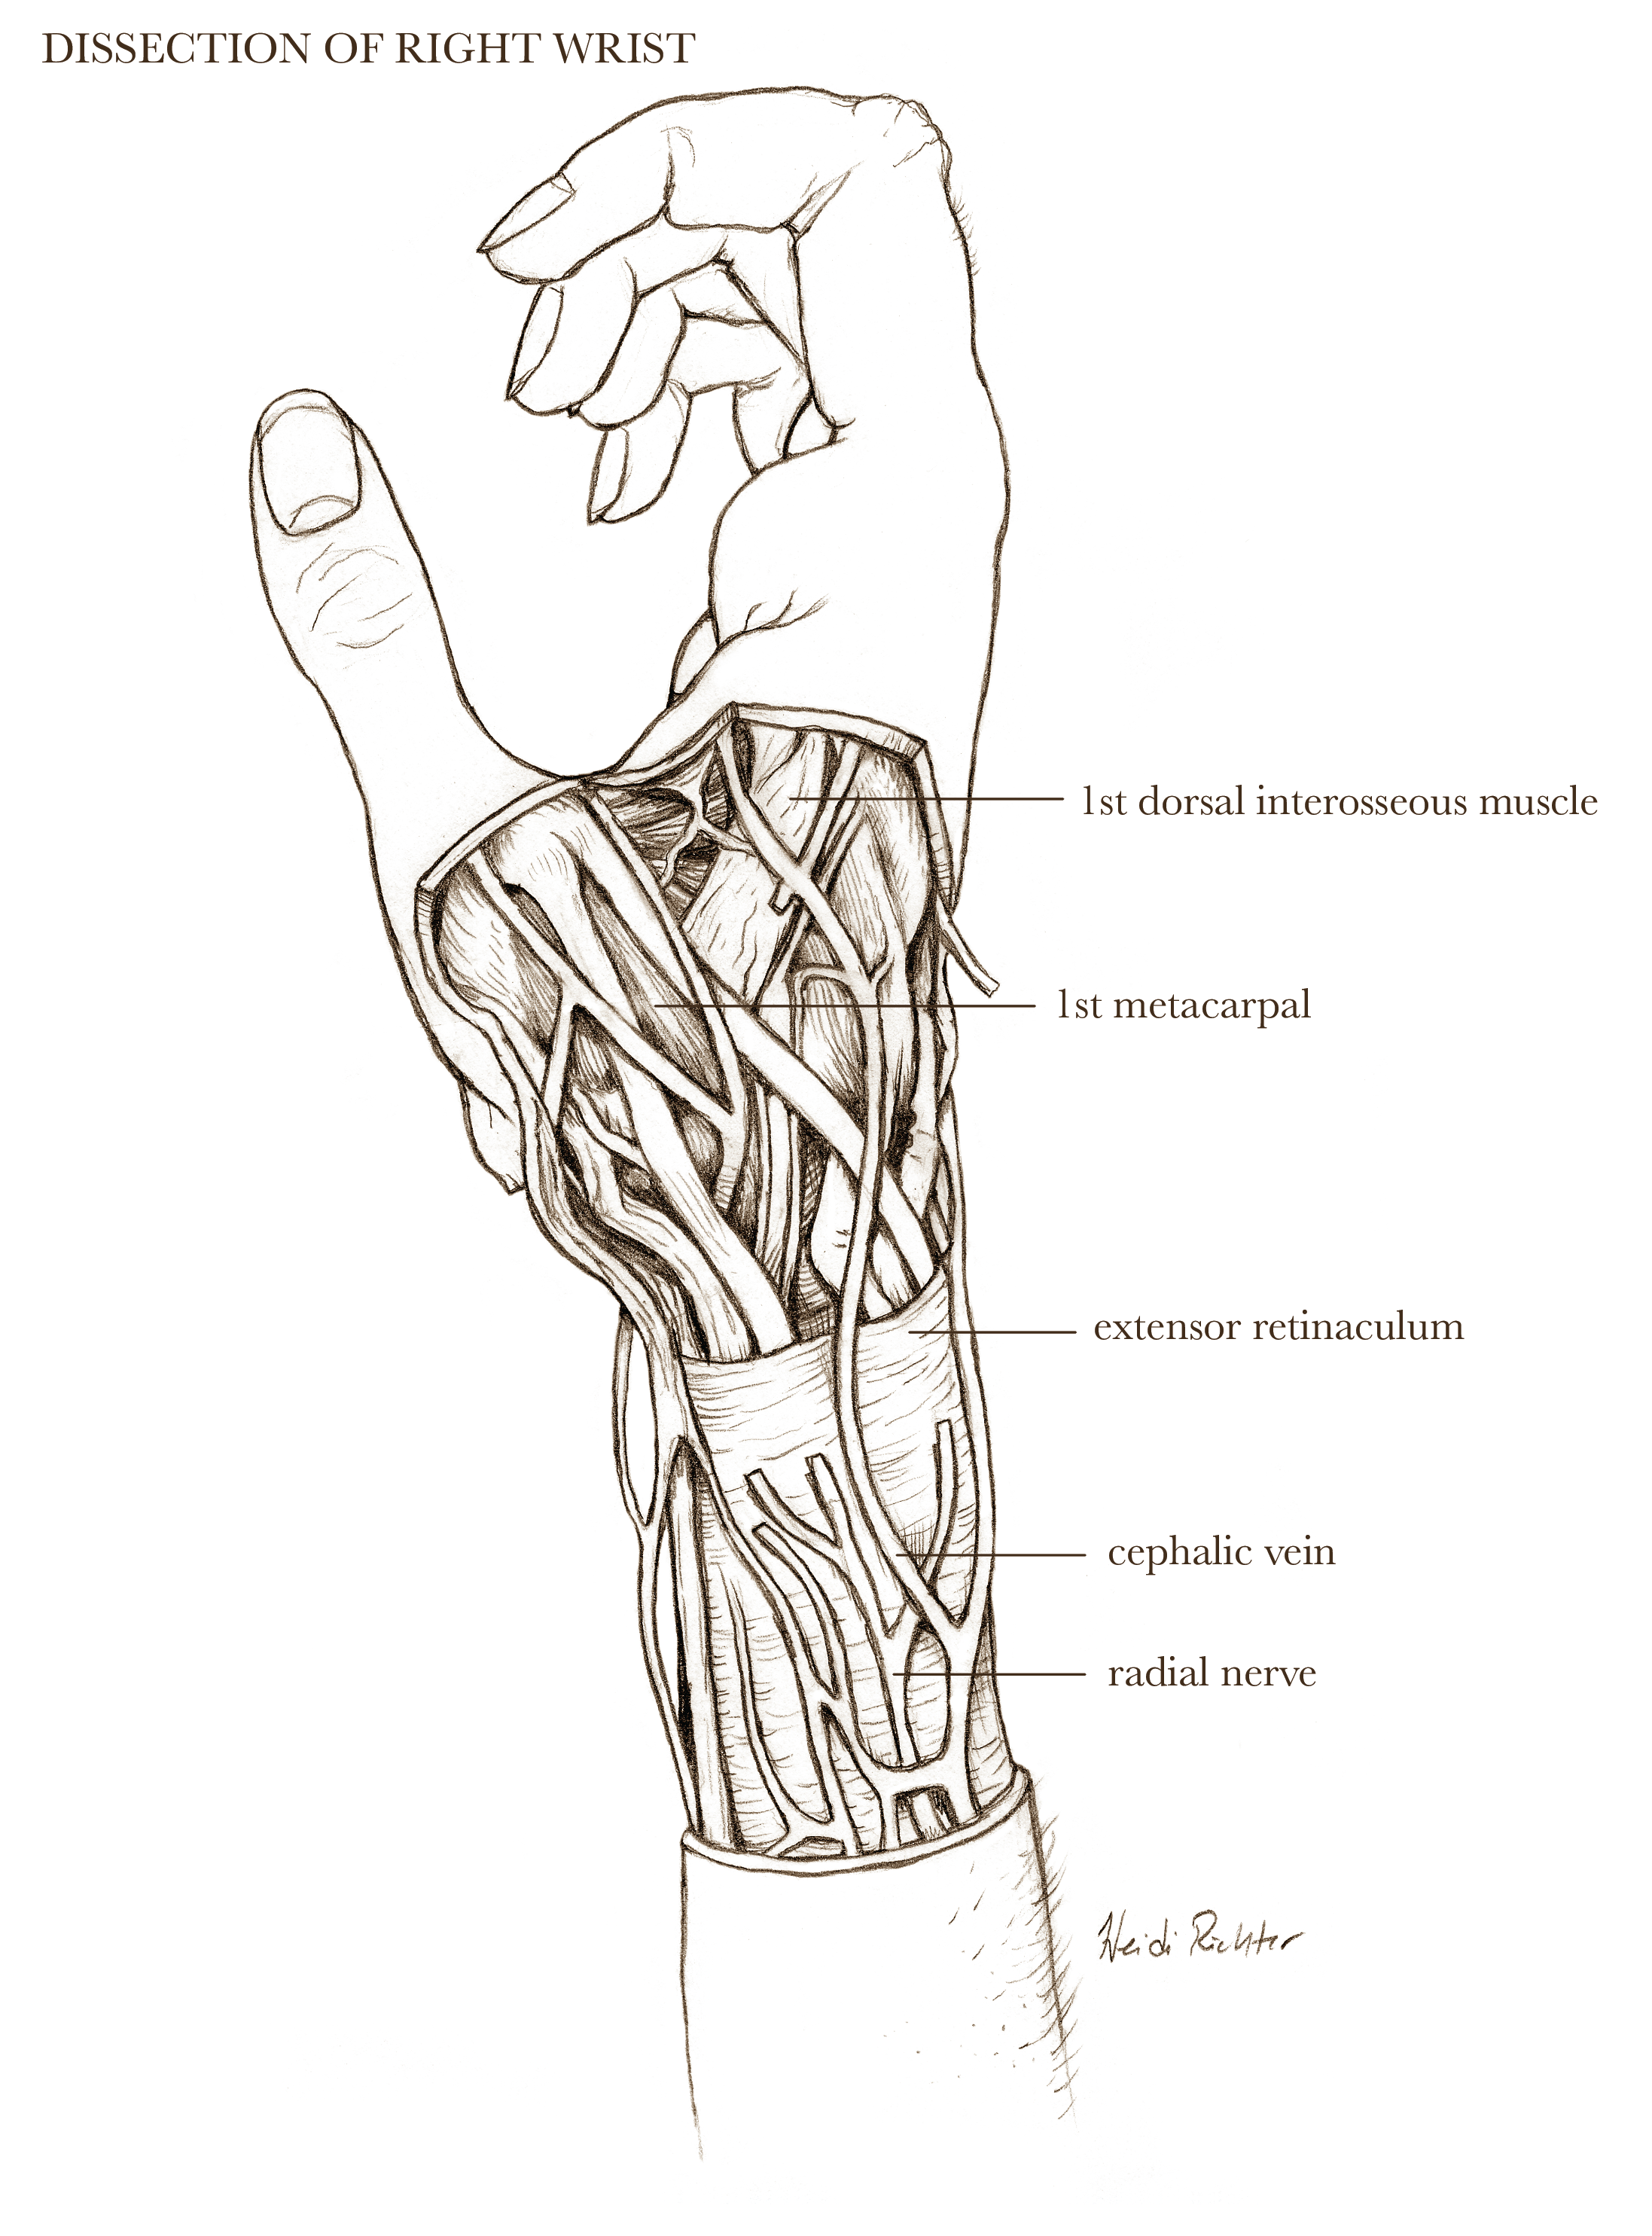

Textbook illustration

I have nearly twenty years of experience in text book publishing, having illustrated books from grade school to graduate level, and in subject areas from human anatomy to biology and geology. I never say no to projects involving dinosaurs.

Medical-legal illustration

I can create client-specific illustrations for your personal injury or malpractice cases to both inform the jury (who often don’t have experience with hospital images) as well as gain sympathy for the affected individual. I can work directly with medical experts to ensure accuracy and admissibility in court.

Illustrations shown below are owned by the artist and available for non-exclusive licenses, contact me for more information.